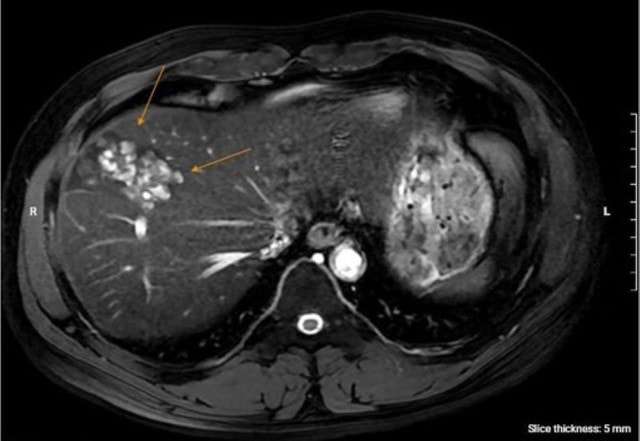

Để làm rõ chẩn đoán, bác sĩ chỉ định ông N. chụp cộng hưởng từ (MRI) ổ bụng, kết quả phát hiện nhiều ổ tổn thương khu trú gan phải, dạng hoại tử dịch hóa nhiều ổ, nghi ngờ do ký sinh trùng. Đồng thời, xét nghiệm chuyên sâu xác nhận dương tính với sán lá gan lớn và giun lươn.